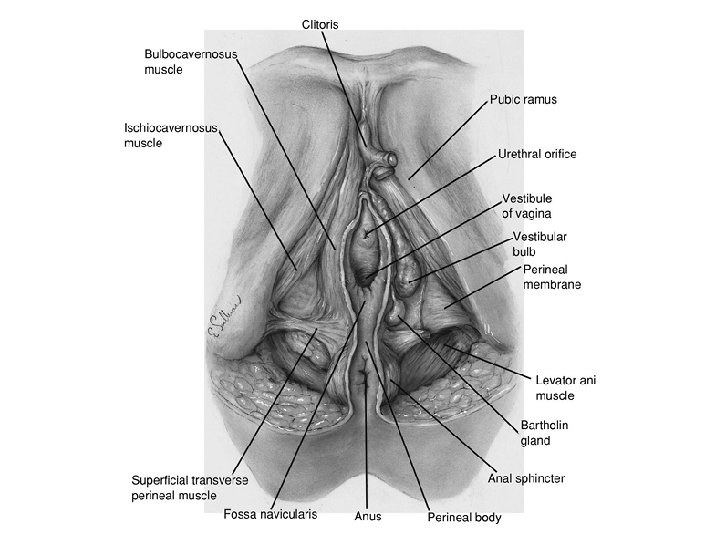

Layers of the Anterior Triangle of the Perineum • Skin • Subcutaneous tissue . Camper's fascia . Colles fascia • Superficial space . Clitoris and its crura . Ischiocavernous muscle . Vestibular bulb . Bulbocavernous muscle . Greater vestibular gland . Superficial transverse perineal muscle • Deep space-perineal membrane . Compressor urethrae . Urethrovaginal sphincter

• Ürogenital trigon: – – M. Transversus perinei superficialis M. İschiocavernosus M. Bulbocavernosus M. Transversus perinei profundus • Anal trigon: – M. Levator ani – M. Sphincter ani externus

FIGURE 7. 2. Superficial compartment and perineal membrane.

FIGURE 7. 2. Superficial compartment and perineal membrane.